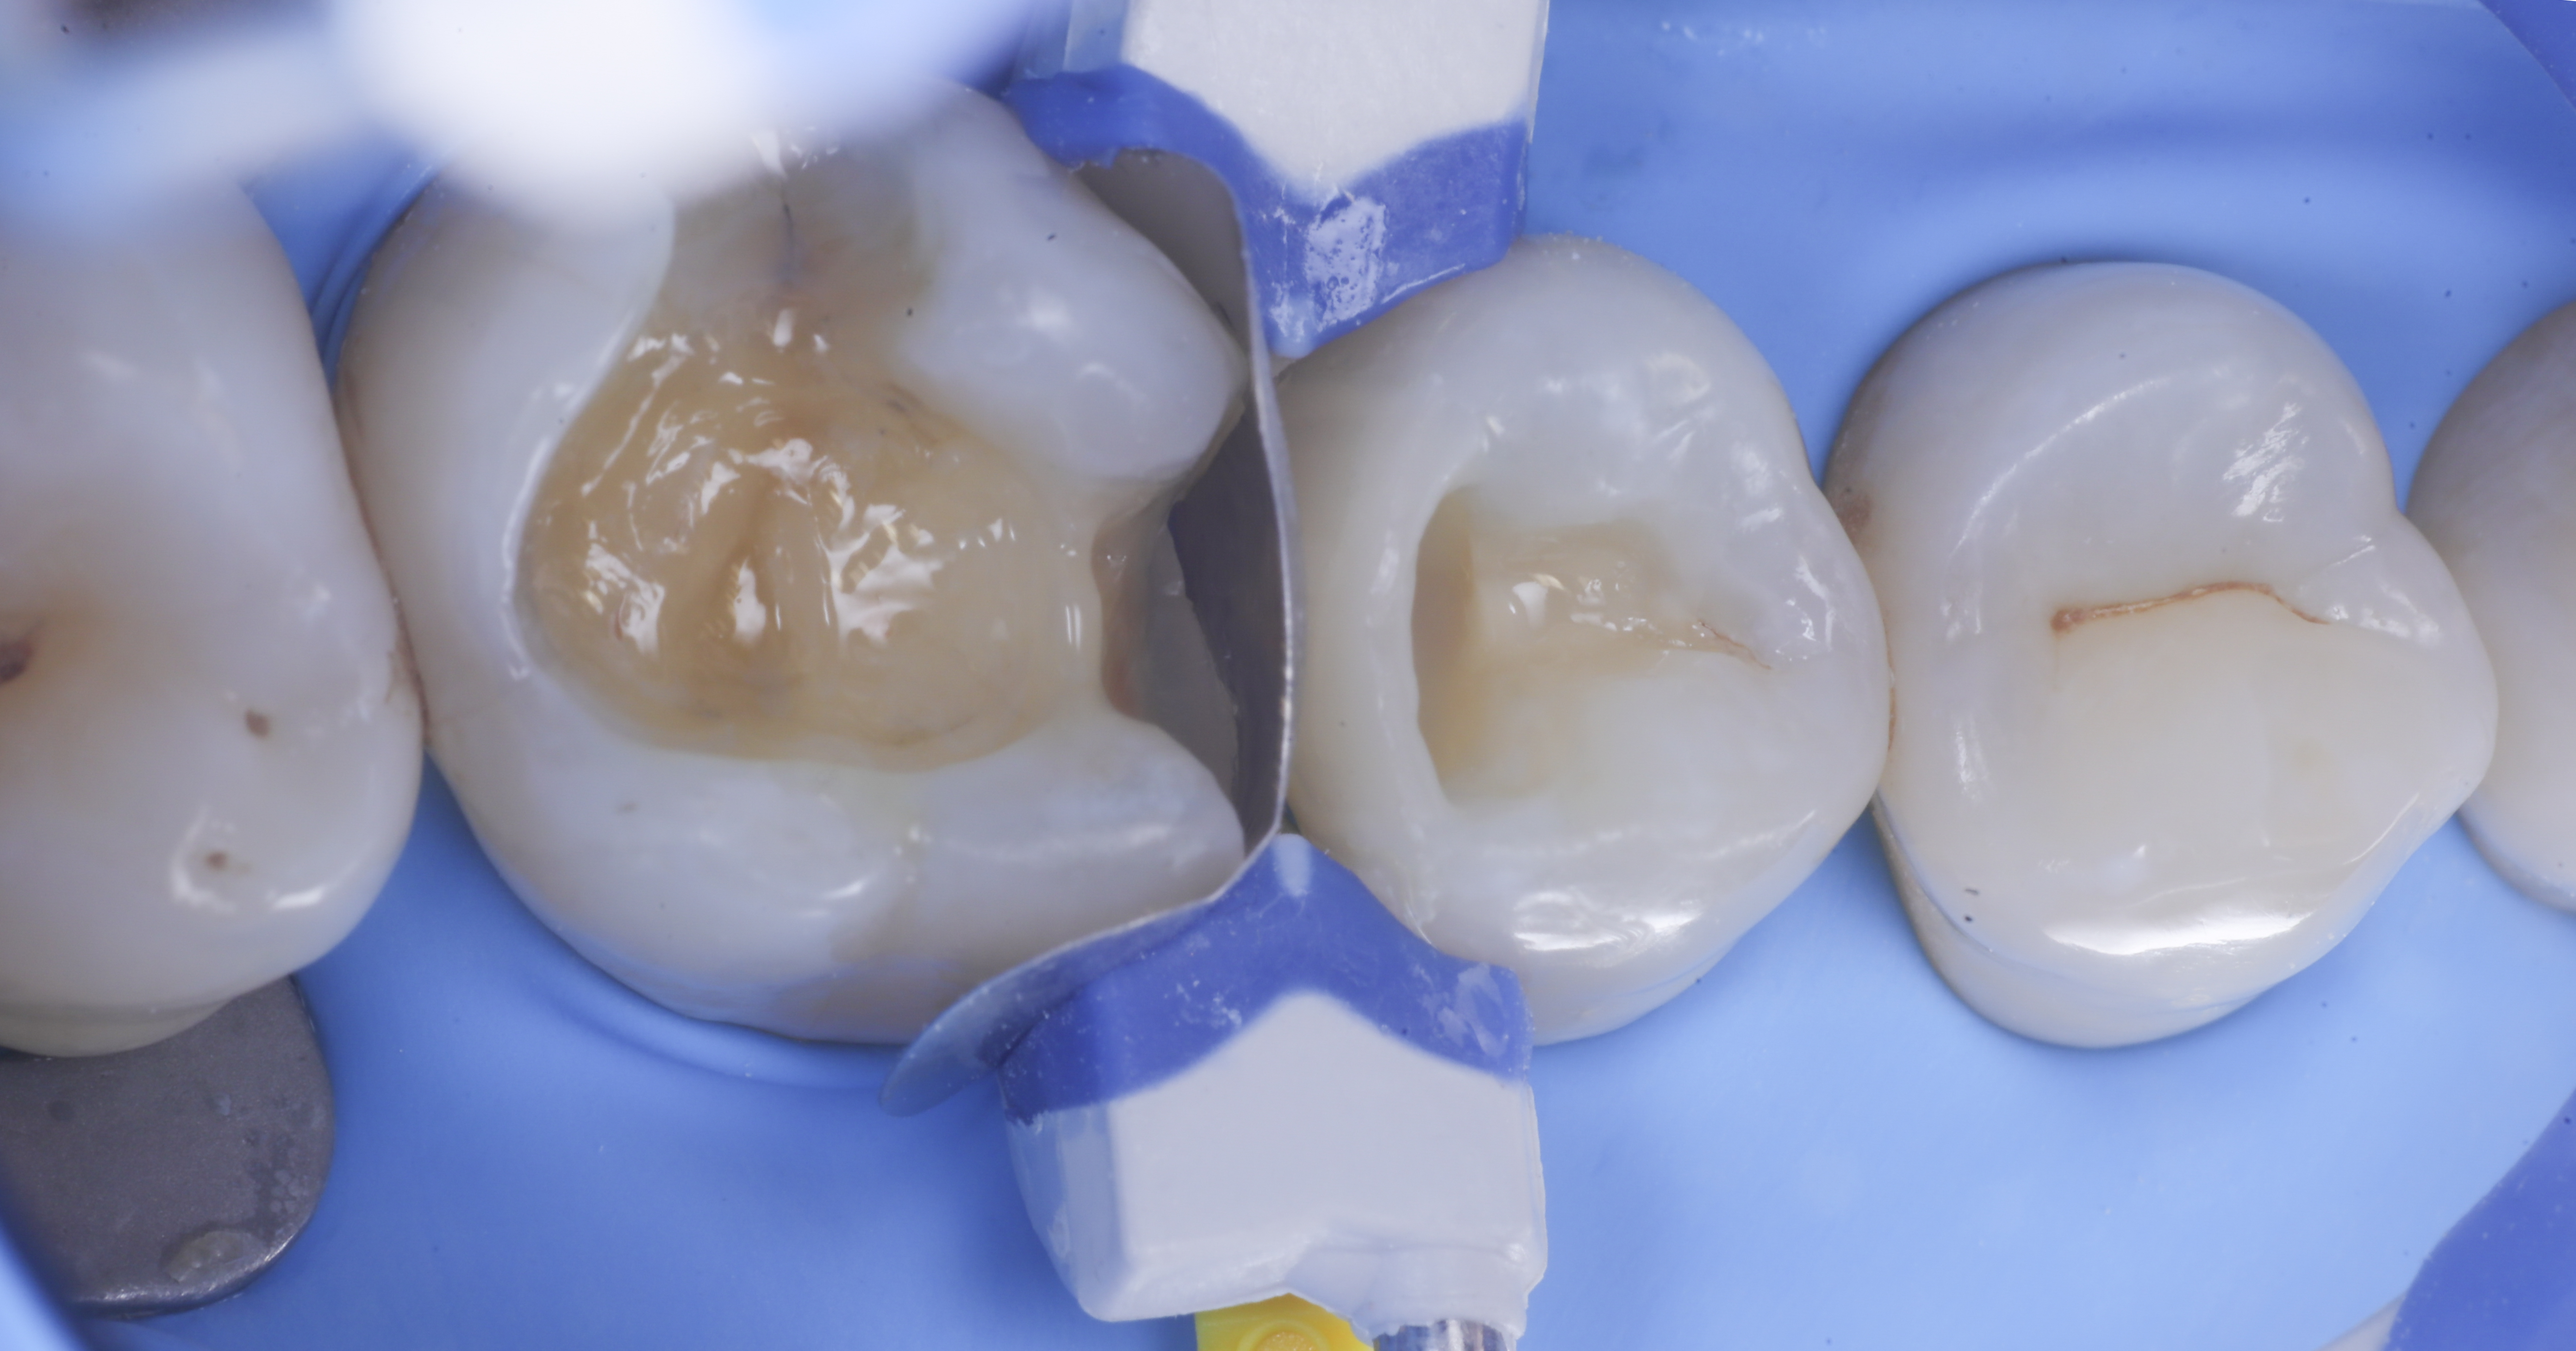

foto 2 Isolamento e aspetto delle cavità ultimate

foto 4 Aspetto della chiusura cervicale e sulle pareti assiali dato dalla prima matrice

foto 5 Aspetto della chiusura cervicale e sulle pareti assiali della seconda matrice